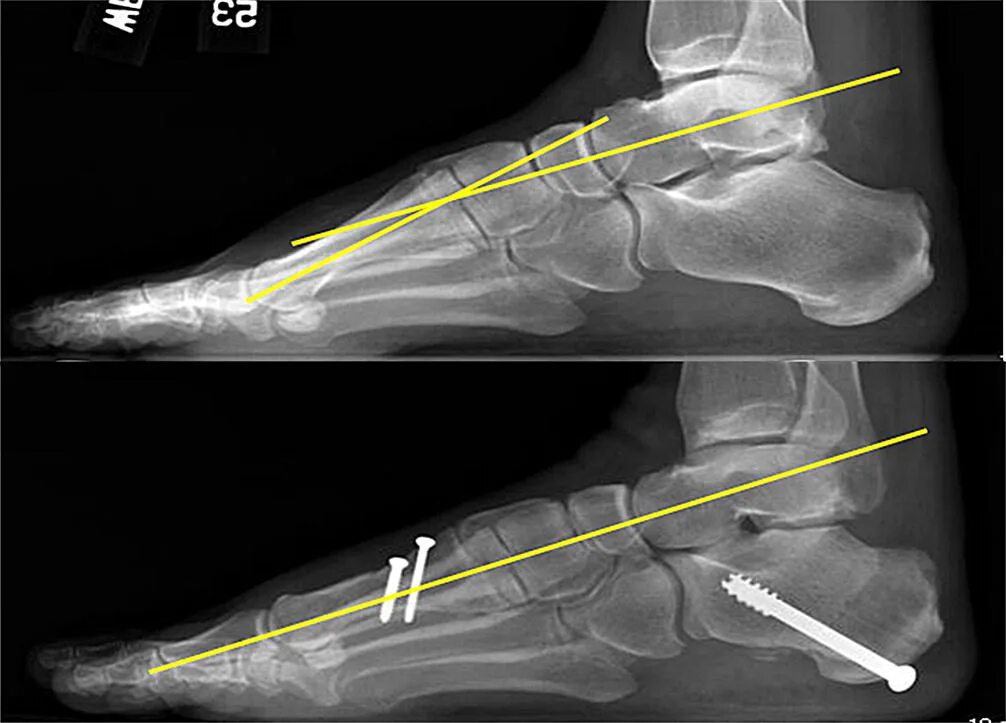

Пяточная остеотомия